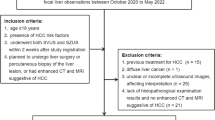

Although ultrasound has been advocated for HCC screening, no standardized or recommended means of performing or reporting the exams previously existed until recently. In 2014, US LI-RADS was created to provide a standardized lexicon, technical recommendations, and a reporting guide for findings, which are tied to management recommendations (Fig. 1 [8]). The technical recommendations of US LI-RADS provide suggestions for equipment and patient parameters as well as a list of suggested sonographic windows, imaging techniques, and images to assure complete coverage of the liver. These recommendations attempt to increase the quality and reproducibility of the exam and ultimately, the accuracy of ultrasound screening and surveillance. Once the exam is performed, US LI-RADS provides a category score of 1, 2, or 3 reflecting findings (termed observations) and suggested management. A category 1 exam contains no observations suspicious for HCC and places the patient at routine screening in six months. Category 2 exams have a subthreshold observation, usually less than 1 cm for which a 3–6-month follow-up exam is suggested, while category 3 exams have an observation for which a contrast-enhanced exam (either CEUS, CT, or MRI) is required for further evaluation. LI-RADS also provides a visualization score meant to convey the expected sensitivity of ultrasound for visualization of the liver and detection of HCC. Here, visualization score A is an exam with little limitation, B is moderate limitation, and C is severe limitation for the detection of HCC (Fig. 1. Category scores 1,2,3 and visualization scores A,B,C). Examples of these classifications are provided in Fig. 2. In this way, exams are technically optimized for HCC detection, exams are assessed for the adequacy of visualization of HCC, and ultimate findings are connected to further management.